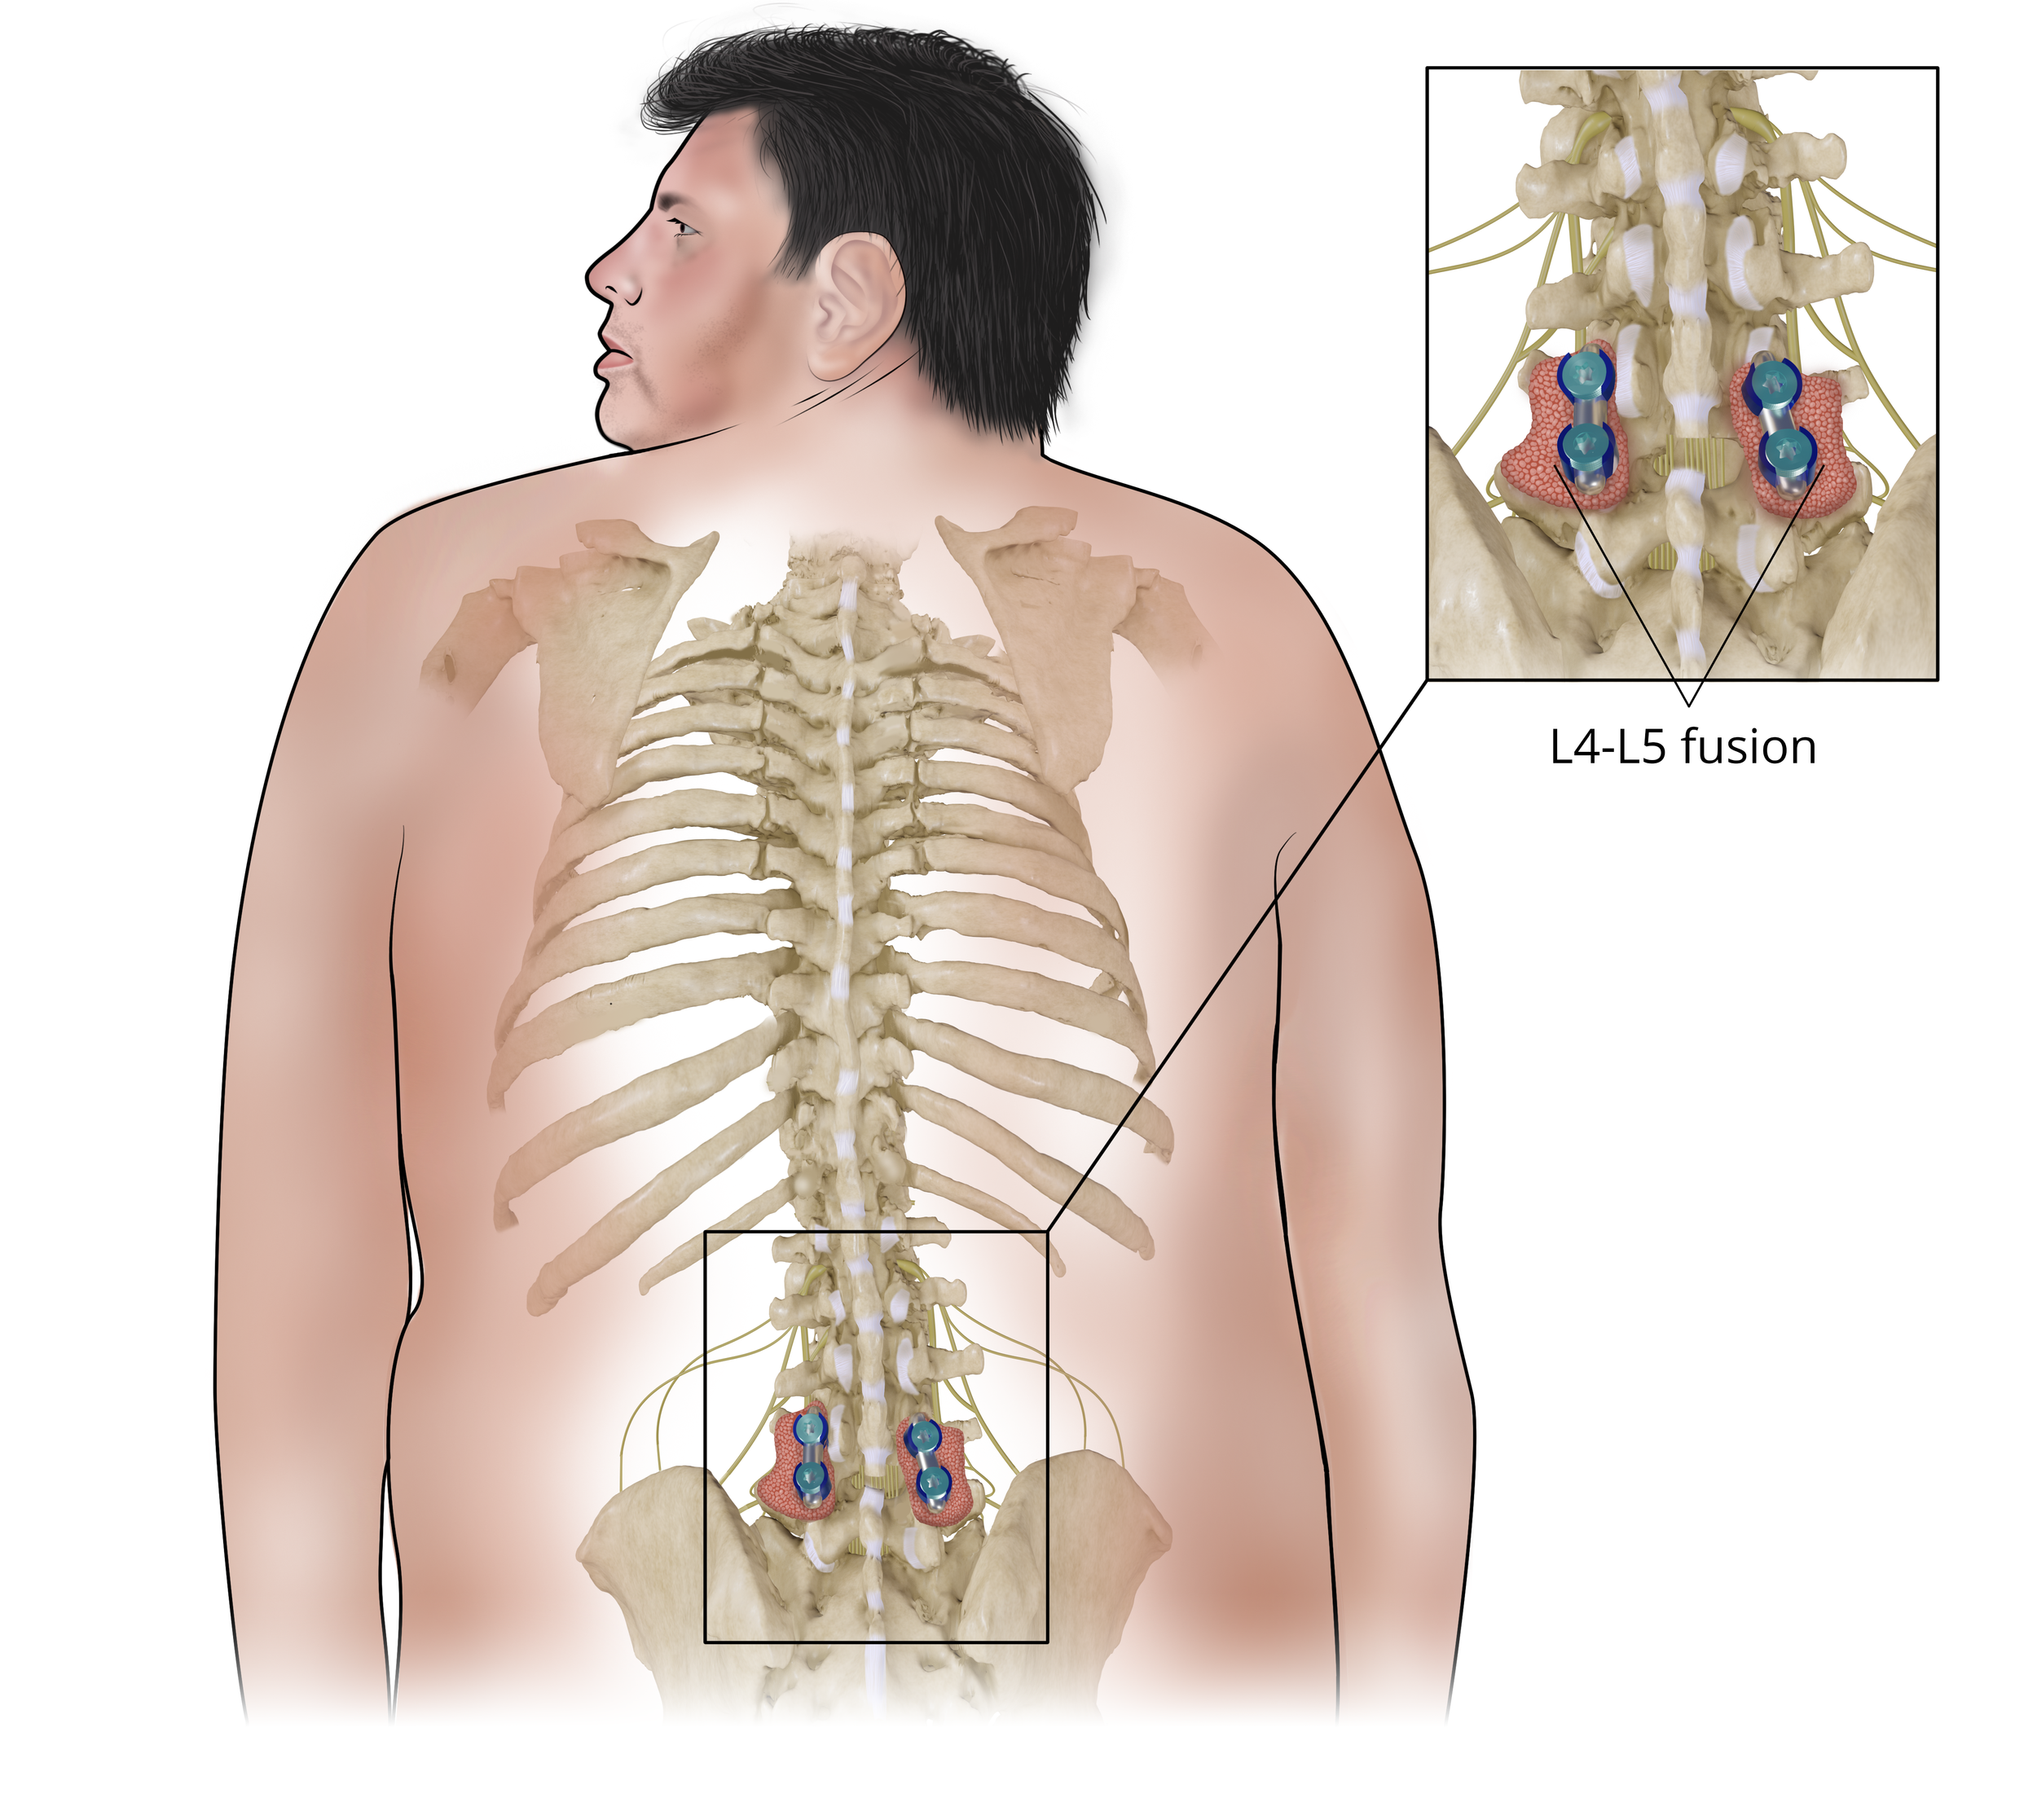

L4-L5 Fusion